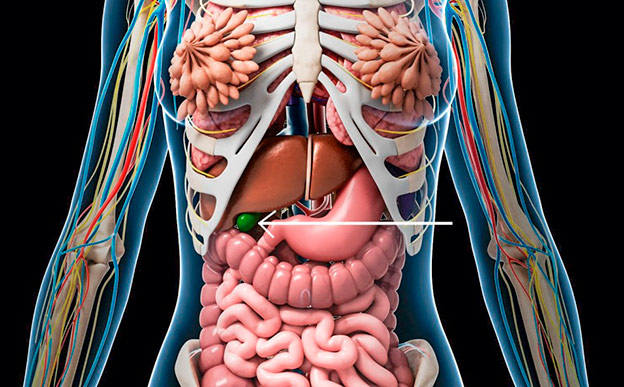

La vesícula

Sí, se puede vivir sin vesícula. La función de este órgano es la de almacenar bilis, un líquido necesario para descomponer las grasas que ingerimos. Ante distintos trastornos –como cálculos, pólipos, pancreatitis o colecistitis– es frecuente que se decida su extirpación. A partir de ese momento será el colédoco –un conducto que va del hígado al intestino– el encargado de realizar sus funciones. Y, según aseguran los expertos, su extirpación no limita la calidad de vida; al contrario, la mejora.